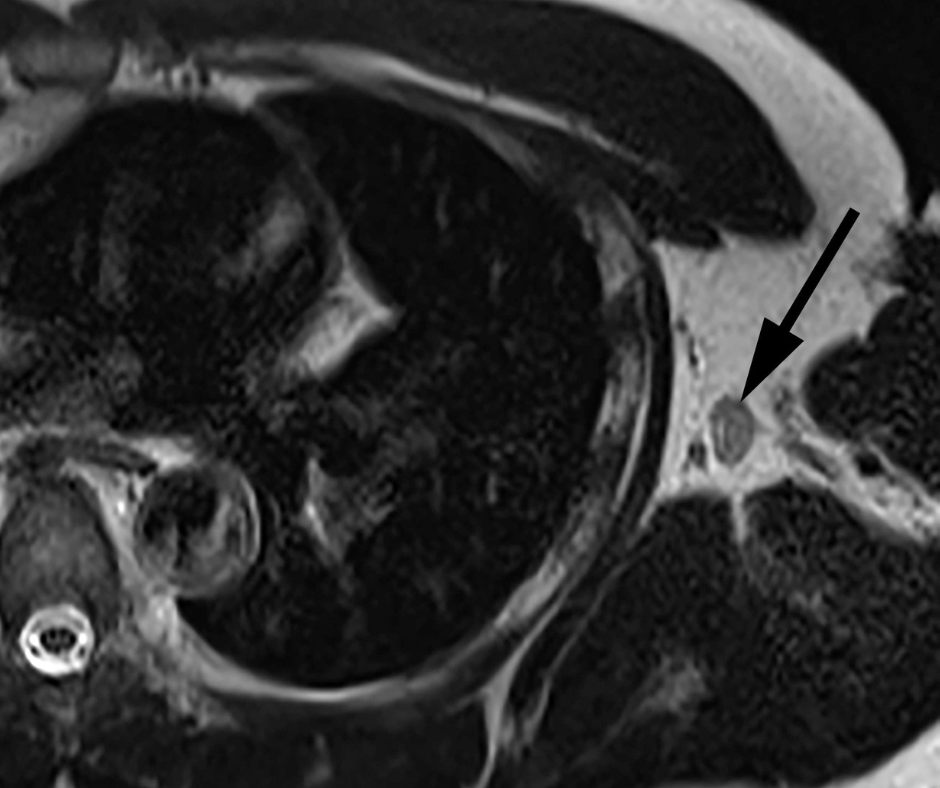

What is the diagnosis?